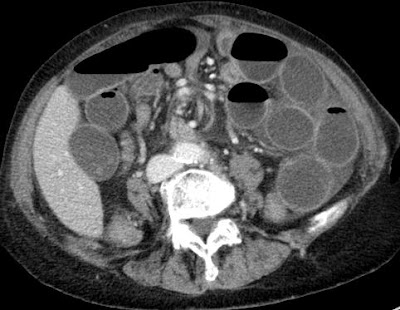

| dilated small bowels according to mesenteric swirl |

| center of the whirl is the superior mesenteric artery |

Whirl sign definition by http://radiology.rsna.org/content/226/1/69.full.pdf :